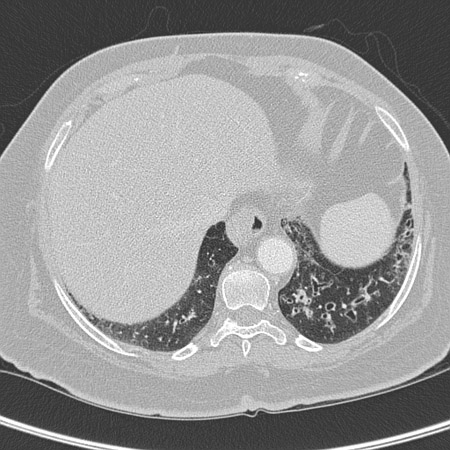

Chest CT showing idiopathic pulmonary fibrosis

From the personal collection of Dr J.C. Munson, Center for Clinical Epidemiology and Biostatistics, University of Pennsylvania School of Medicine